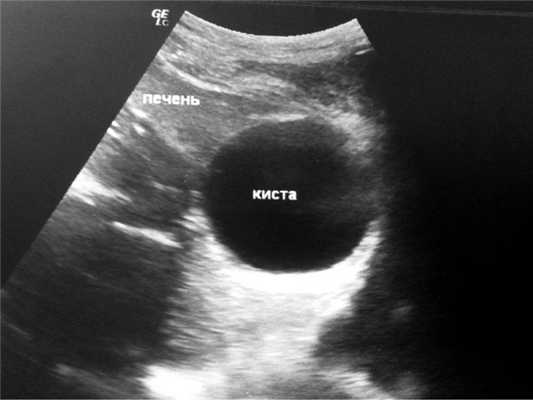

Больной П., 39 лет, госпитализирован в отделение видеоэндоскопической хирургии ГКП на ПХВ «Мангистауская областная больница» (г. Актау, Казахстан) с подозрением на острый живот. При поступлении жаловался на боли в правом подреберье. За несколько часов до поступления был сильный кашель (во время приема пищи больной поперхнулся), в момент которого появились резкие боли в правом подреберье. Через 10—15 мин боли в правом подреберье значительно стихли и постепенно сместились в правую подвздошную область. Больной отмечает, что небольшая припухлость в правом подреберье, отмечаемая им ранее, в настоящее время исчезла. Ранее у больного был диагностирован эхинококкоз печени в 5—7-м сегментах СЕ1-типа, по классификации ВОЗ, размерами 6×8 см (рис. 1), по поводу чего готовился к плановой операции.

Рис. 1. Больной П., 39 лет. Эхинококковая киста в проекции 5—7-го сегментов печени до прорыва.